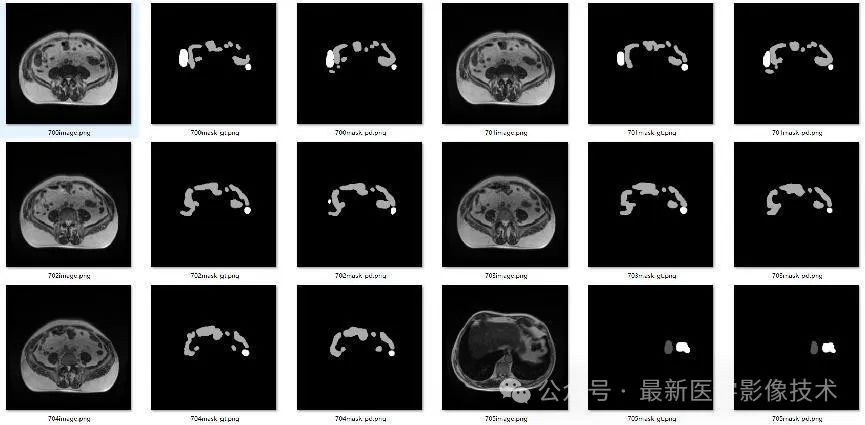

4、验证集部分分割结果